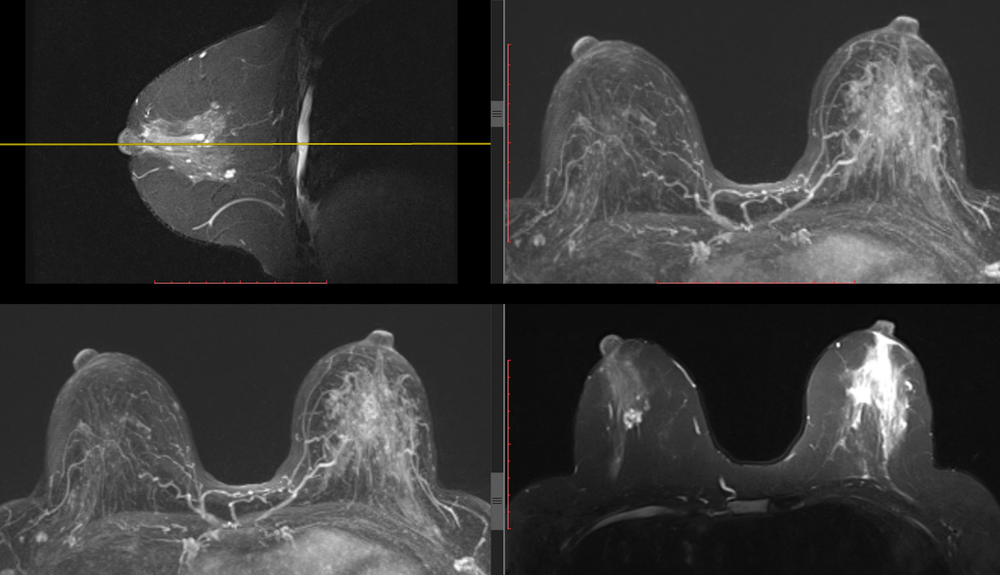

Le point sur l'IRM mammaire en 2019

L’IRM des seins est une technique très performante pour la détection et l’évaluation des tumeurs. Elle ne remplace pas la mammographie ni l’échographie et ne constitue pas un examen systématique du diagnostic du cancer du sein. Il s’agit d’un examen de seconde intention, d’un outil supplémentaire que l’on emploie dans des indications précises.

La classification BI-RADS® IRM mammaire est basée sur des critères morphologiques (masse, rehaussement sans masse, focus), des critères cinétiques (le profil dynamique du rehaussement dans sa phase initiale (2 minutes) et sa phase tardive) et les signes associés. Suivant cette classification, une conduite à tenir est proposée.